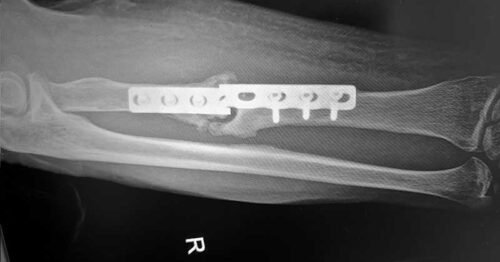

رفع الشرائح و المسامير

من الشائع أن يتم تثبيت الكسور بإستخدام شرائح و مسامير أو مسامير نخاعية. و الهدف من هذه الشرائح و المسامير هو تثبيت الكسر فى الوضع المثالي له بدلاً من ربطه بالجبس الى أن يلتئم مع السماح للمريض بتحريك مفاصله حتى لا تتيبس. و بعد إلتئام الكسور تصبح هذه الشرائح بلا فائدة. فهل يتوجب إزالتها من الجسم بعد ذلك؟

فى الواقع أنه فى اغلب الحالات لا يتم رفع الشرائح و المسامير حيث أنها مصنوعه من مواد لا تتفاعل مع الجسم و لا تسبب له أي مضار صحية له بمرور الوقت. و لكن هناك بعض الحالات التي تستلزم رفع الشرائح: